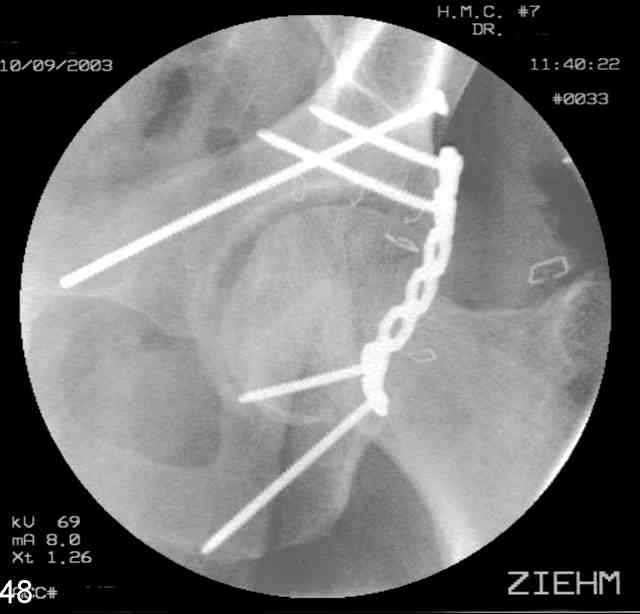

You can adjust the quadrilateral surface contact point as needed to get the fracture to reduce...we plan this based on the fracture orientation on the preop CT scan images...the clamp should be balanced to avoid over compressing one portion and distracting the other limb. Go back to and you¹ll see on the injury CT where the clamp tines need to be.

Prone

Here's a pic from the foot of the bed and you can see the clamp in the wound and the knee is extended so he must've had a tight rectus. The C-arm is rolled back to an obturator oblique image to reveal the anterior column...we put a slight outlet tilt to combine the images and give a better view of the anterior column...we can see the posterior column limb reduction in the wound, we can palpate the quadrilateral surface limb, and the image demonstrates the anterior column portion...you can adjust the tilt and rotation to image tangentially to the fracture plane if you'd like. We've inserted a 2mm K wire to site the starting point and aim/orientation for the drill and screw

Prone Imaging

same image, just another look.

Prone Inlet

OK, now we're inserting the drill percutaneosuy using a sleeve. This fluoro shot is not for this patient (notice no clamp) but I was too lazy to go searching the PACS for one with the clamp on, so pretend...I'll save the next ones and send along...the imaging is the same and the clamp doesn't obstruct imaging other than very rarely...you can always tilt the C-arm a bit to clear it if the clamp obstructs the exact spot that you'd like to see. We'll assume that everyone knows the safe zone for a medullary ramus screw. Use a calibrated drill and sleeve of known length to simplify your life...or use Alex's fancy cannulated screws...I like 3.5mm screws because the oscillating 2.5mm drill bounces and remains intraosseus when it oscillates and contacts endosteal cortical ramus... so will the screw, and like a long bent screw IF the fracture is clamped... if unclamped, when the screw contacts the endosteum, it pushes the reduction apart instead of bouncing. The big 7mm cannulated screws fit few patients and extrude...we very rarely use them any more...you'll see an old one later.

Prone Obturator-Outlet

Screw insertion using the obturator-outlet combination image.

12.Prone Obturator-Outlet

Same with a contoured pelvic reconstruction plate applied and tensioned.

Prone Iliac Oblique

The other oblique reveals the extra-articular implants.... you know the AC screw is extra-articular from the other views.

Routine Fixation

AC Screw

PC Neutr Plate

Others

The unstable caudal segment is secured by the lower 2 plate screws and the AC medullary screw... always assure that your fixation is sufficient to defeat the instability... part of your prop plan... but assure it before you close... it¹s your last chance... you shouldn't have to be pushing on the hip in contorted ways to determine your fixation stability...you can if that makes you 'comfortable'.

A CT scan will rarely lie to you...reveals your reduction and implants...we use it to assess, teach, grade, and try to get better next time.

Dorsal Selective Clamp

Yuk, the Farabeuf clamp...a selective dorsal clamp applied using cortical screws previously inserted into the best balance zone of the posterior column... sometimes helpful, and always in the way.

-PCol Compress

-ACol Distract

-Central

-Joint Screws

-Obstructive

-Sciatic Nerve

The Farabeuf compresses the posterior column limb and this maneuver usually distracts the anterior column component... just like you'd expect it to... the clamp screws are either quite short, directed away from the joint worsening the ACol distraction, or mistakenly inserted into the

joint. The clamp also contacts most sciatic nerves while it's in and unprotected.

Screw Fixation

-AC Screw

-PC Screw

For Alex... here are some cannulated and 7mm screws for you... notice the fracture malreduction as indicated by the head subluxation on both views...this was a percutaneous technique without open reduction... I don¹t like it but there it is... the fixation technique is not at fault, because there was no open reduction of the fracture... but let¹s not get in to all that.